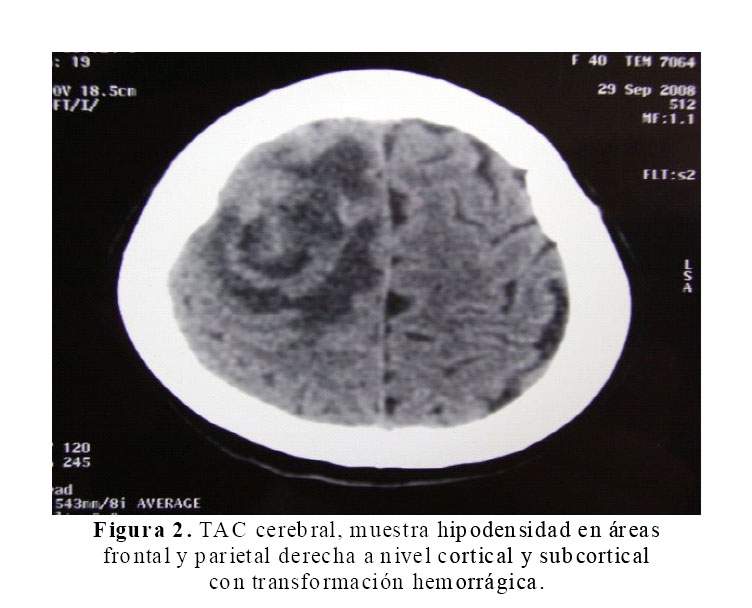

La Rx del tórax mostró cardiomegalia masiva y congestión pulmonar (Figura 1). En la tomografía cerebral se evidenció una hipodensidad en áreas frontales y parietales derechas a nivel cortical y subcortical con transformación hemorrágica (Figura 2). La ecocardiografia era muy similar a la previa, con dilatación e hipocinesia global y fracción de eyección de 25% (Figura 3).

En el caso, la paciente sufrió el accidente cerebro vascular (ACV) a las 12 semanas después del parto. El ACV clínicamente comprometía todo el hemicuerpo izquierdo con un plejia densa y de inicio súbito (Figura 2). La incidencia descrita de ACV en mujeres no gestantes de 15 a 44 años es de 10,7 por 100 000 mujeres (11), mientras la incidencia en el embarazo es de 4,3–210 por 100 000 partos (12). Por el tiempo descrito desde el inicio de la enfermedad actual, se alejarían causas como trombosis venosa cerebral y angiopatía cerebral postparto (11). Debemos tener en cuenta que nuestra paciente desarrolló el ACV pasado el tiempo establecido para el puerperio inclusive.